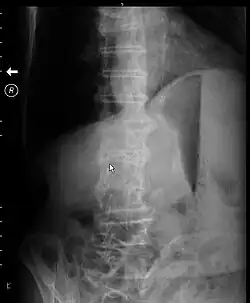

| X-ray of abdomen of a person with gastric outlet obstruction taken while on their side. There is a prominent gastric air bubble, gastric air-fluid level, and a dilated stomach with particulate matter within it. | |

Abdominal X-ray may show a gastric fluid level which would support the diagnosis.